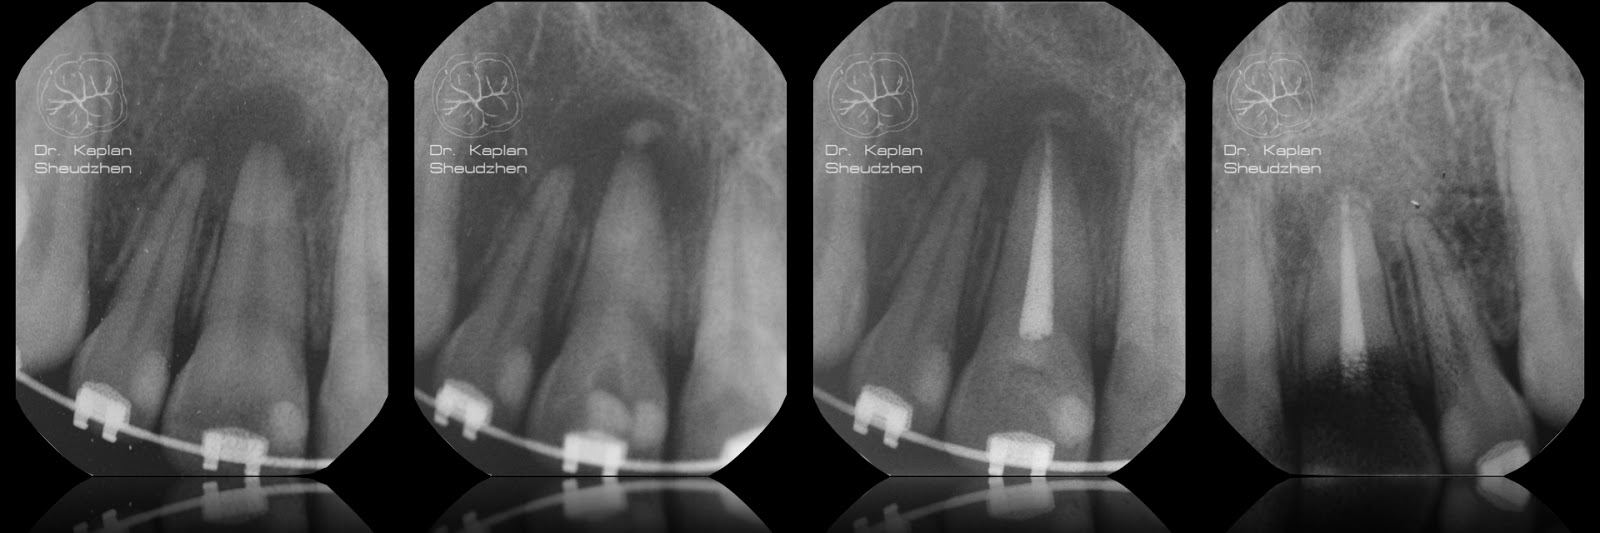

зажило